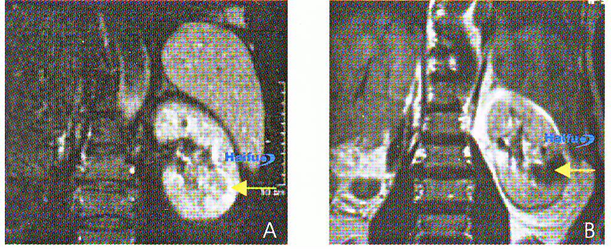

12. МРТ (Т1 ви) с контрастным усилением гандолинием у 66-летнего пациента с почечным раком единственной почки.

А) Коронарный срез до проведения HIFU. В опухоли определяется контрастное усиление (стрелка). В) Через 2 недели после HIFU. Накопление контрастного препарата в опухоли не определяется (коагуляционный некроз) (стрелка).